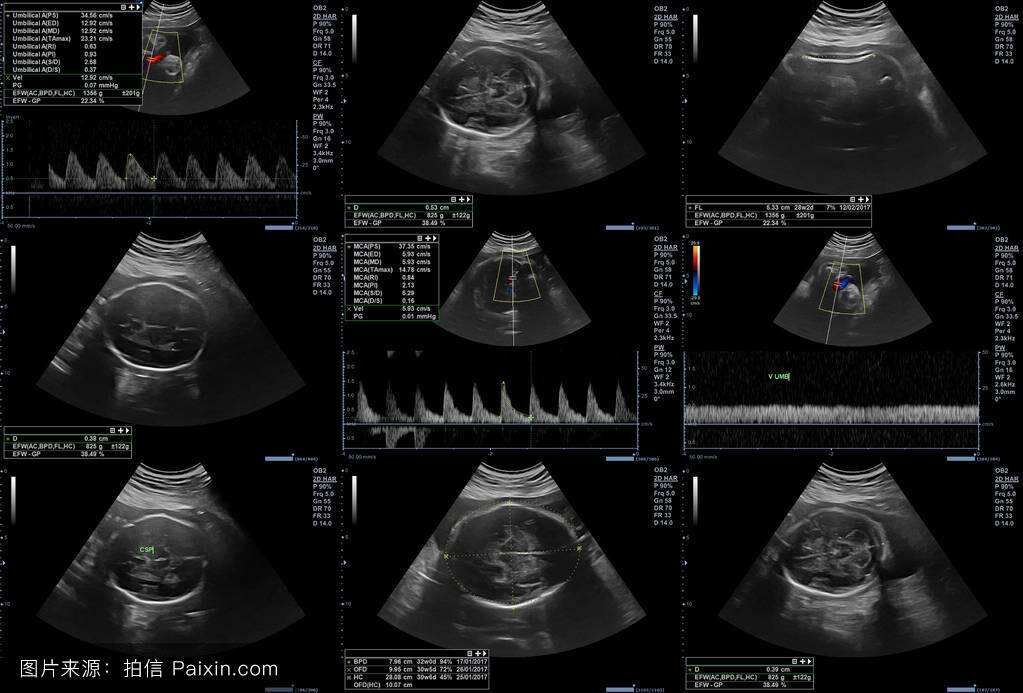

7、胎儿的初级筛查

1、中孕期胎儿三维畸形筛查(排除无脑儿、脑膨出、开放性脊柱裂、胸腹壁缺损、内脏外翻、单腔性、致命性软骨发育严重畸形)